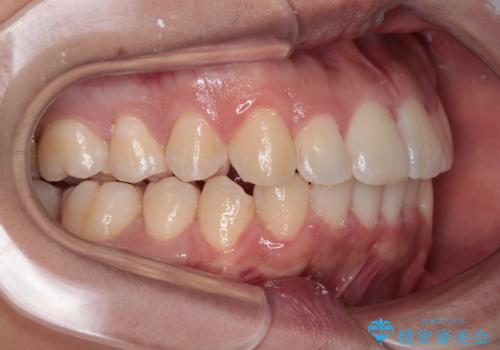

- 前歯のデコボコを治したいとのことで来院された患者様です。

上下顎ともに歯列全体の後方移動とIPR(歯と歯の間を削る)によってデコボコが解消するように設計し、インビザラインにより治療を行うこととしました。

下顎前歯は後戻りを起こしやすいため、舌側を細いワイヤーで固定し、マウスピース型リテーナーで保定を行うこととしました。